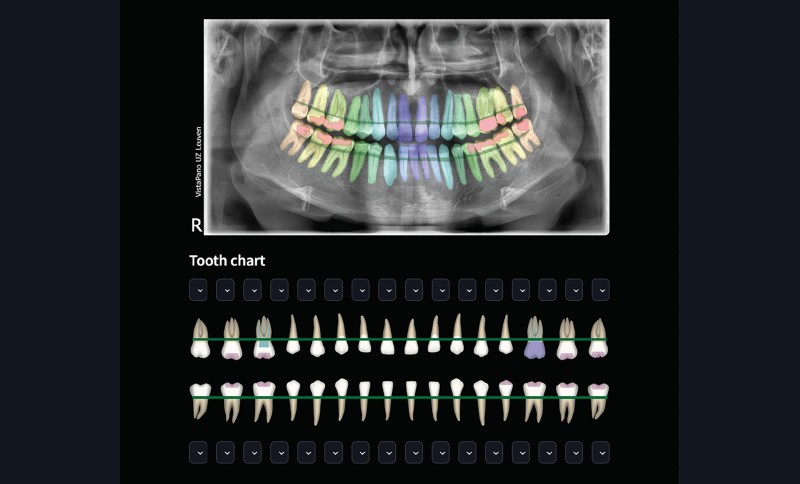

Si l’IA envahit discrètement notre quotidien et que nous, êtres humains, lui faisons de plus en plus confiance, dans la pratique dentaire, nous semblons exprimer plus souvent une certaine méfiance à son égard [1]. Cette méfiance est tout à fait compréhensible, car nos tâches diagnostiques et nos traitements quotidiens exigent un haut degré de précision. En tant que cliniciens, nous ne voulons pas compromettre la qualité des soins prodigués en utilisant l’IA. Cependant, cette dernière peut également être développée sur la base d’un apprentissage supervisé de haut niveau, grâce à une interaction quasi continue et parfaite entre des ingénieurs en IA hautement qualifiés et des dentistes spécialisés. Cette interaction et ces retours d’information sont indispensables pour fournir des renseignements pertinents, non seulement pour le développement de l’IA, mais également pour toute formation complémentaire, validation et résultat clinique [1]. L’IA peut ainsi devenir l’assistant parfait, capable de travailler beaucoup plus rapidement et de manière plus cohérente que le praticien, sans sacrifier la précision [2, 3] (fig. 1). Cependant, l’IA doit être surveillée tout au long de son cycle de vie et apprendre de ses erreurs en étant continuellement soumise à la supervision d’un expert humain à toutes les phases de développement, de validation et de maintenance, avec un retour d’information sur les résultats incorrects renvoyé directement à l’outil d’IA basé sur le cloud. Ce n’est qu’ainsi que l’IA dentaire pourra devenir l’assistant du futur.